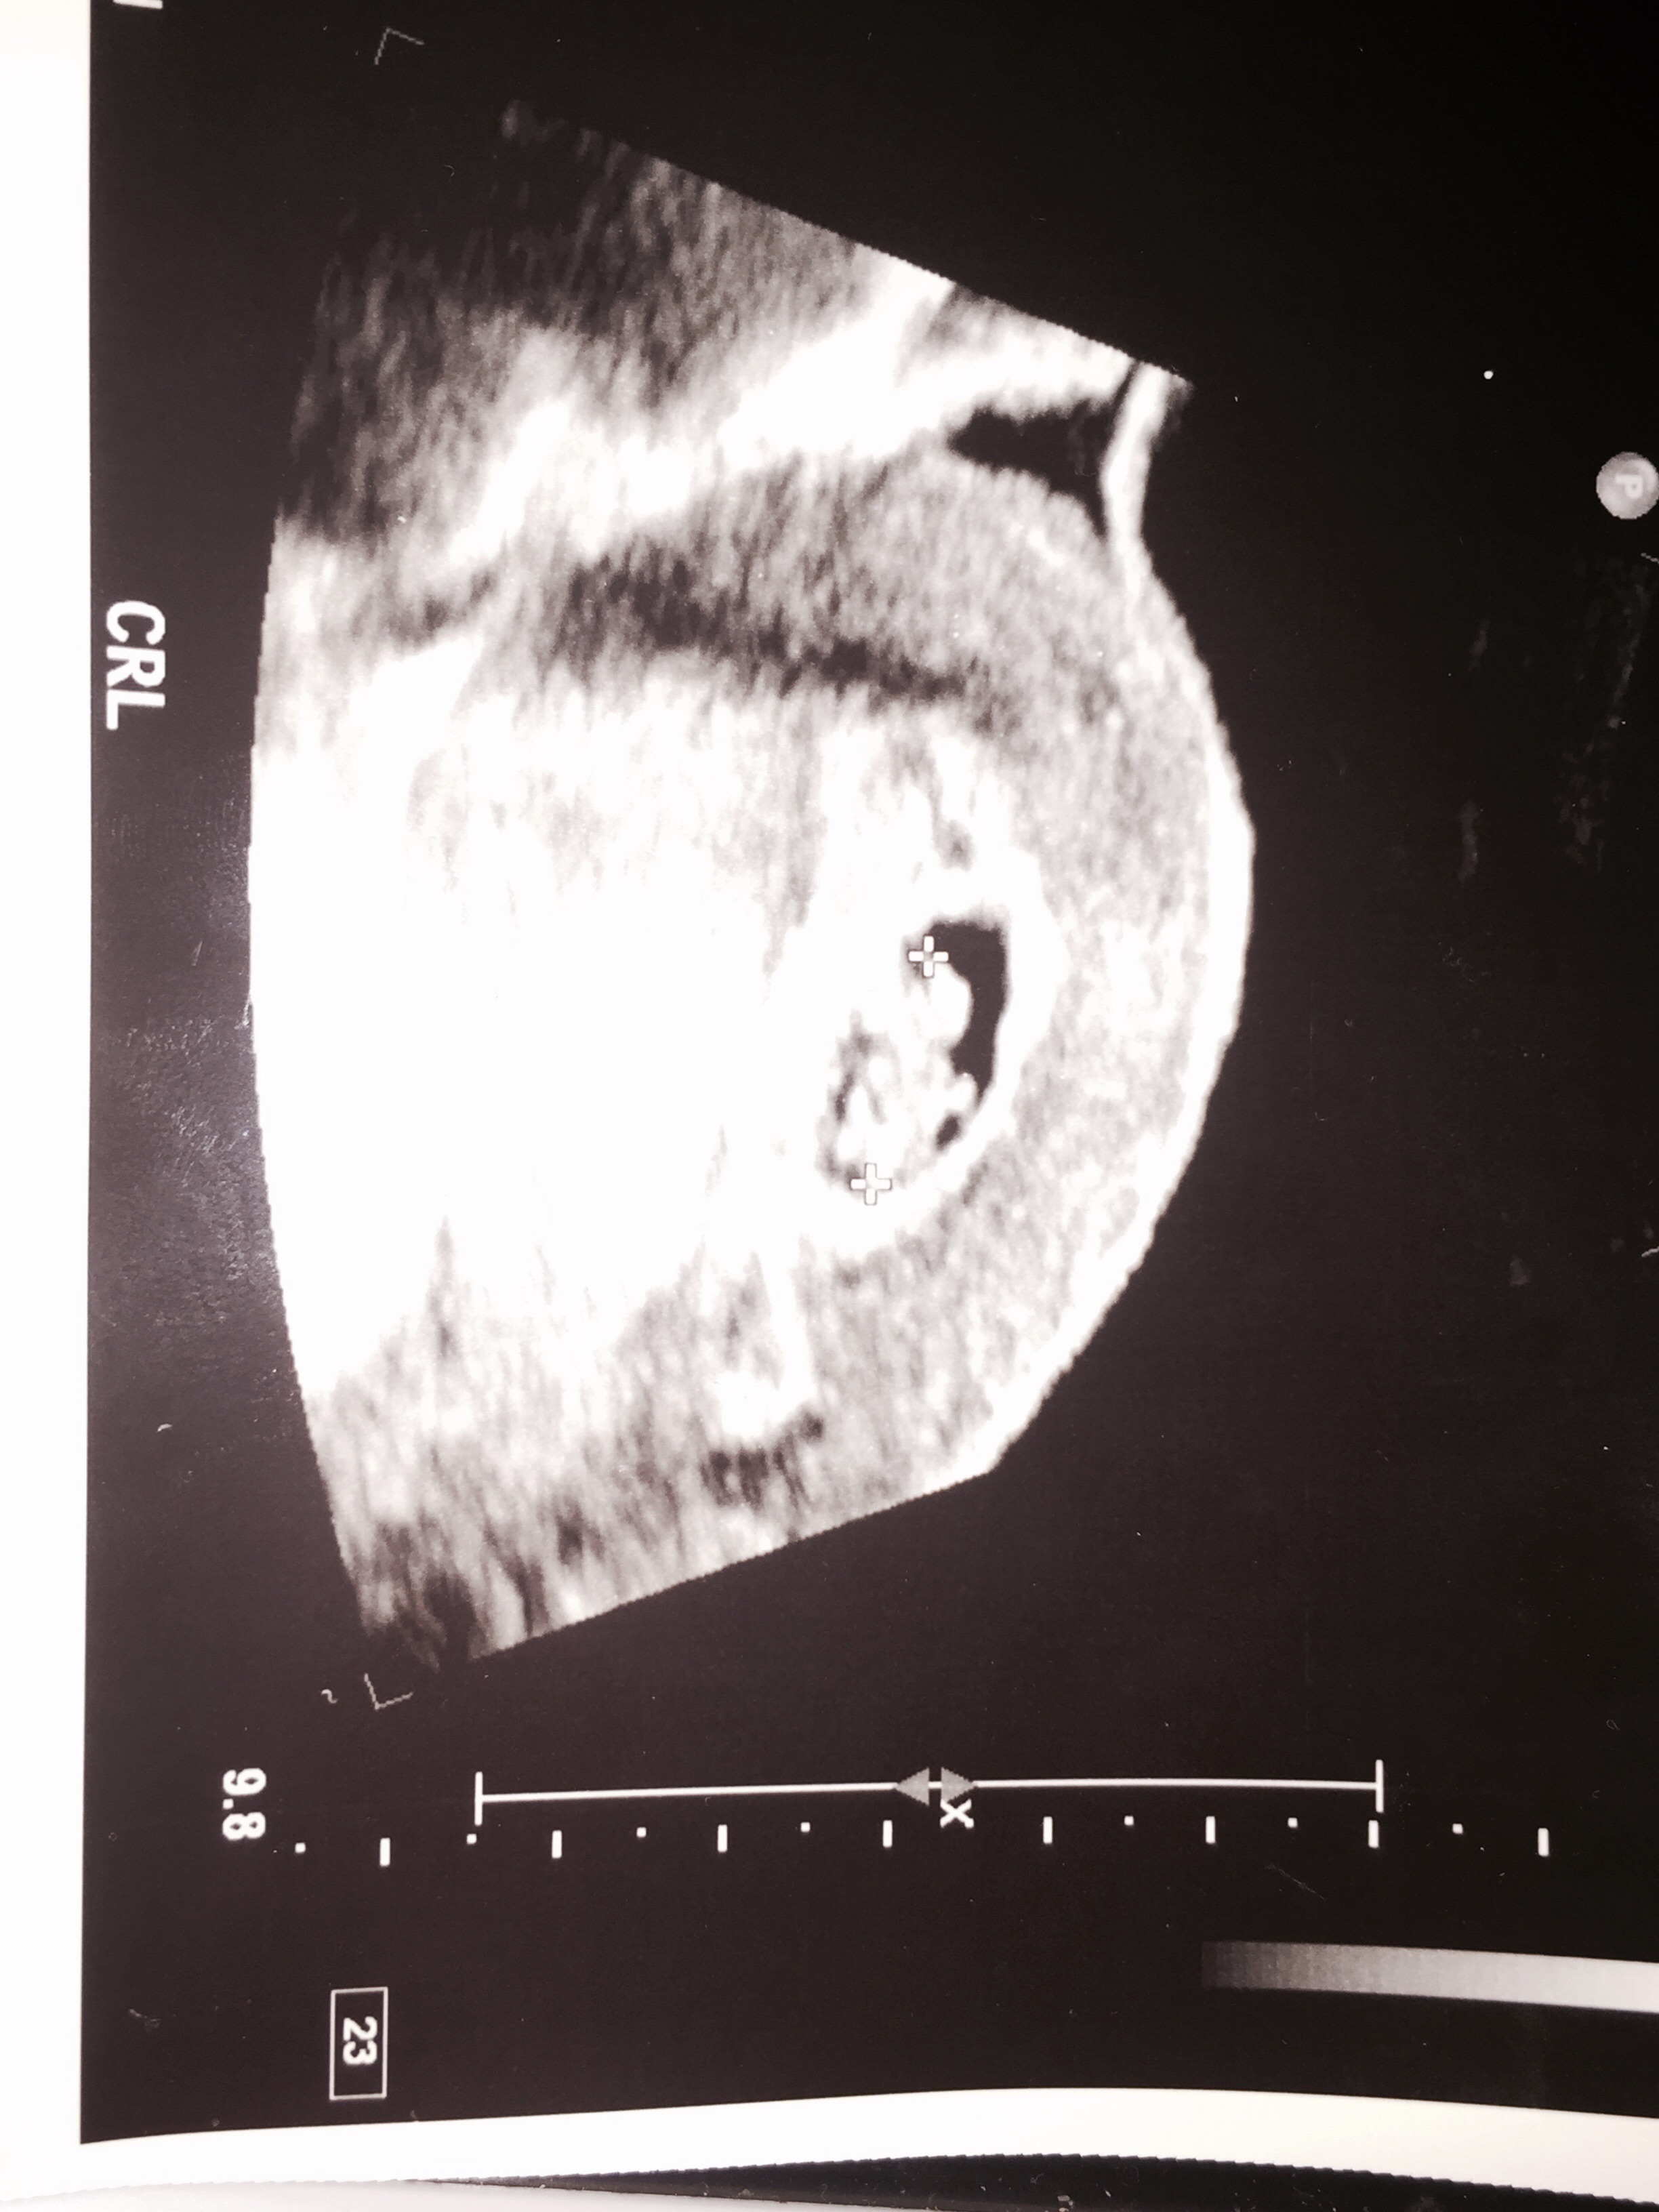

• image

Here is the pic I was given.